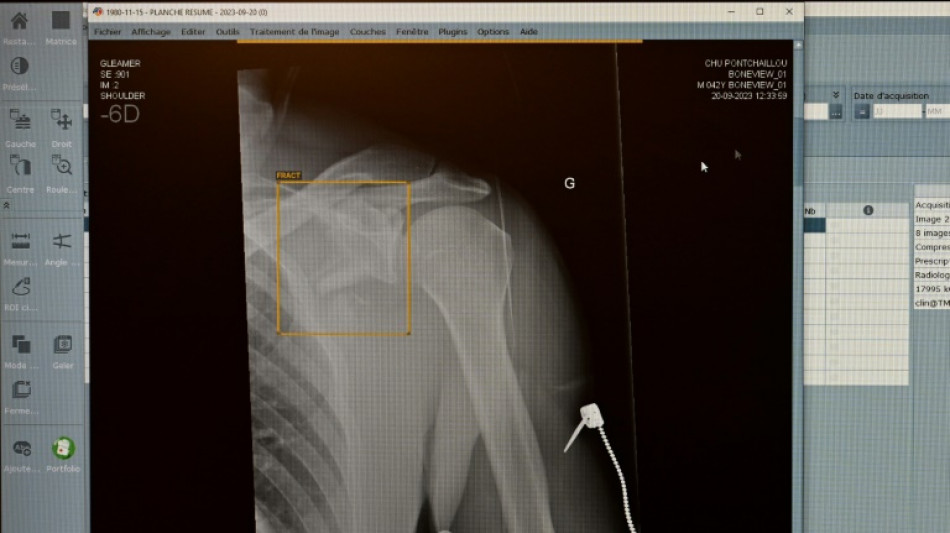

Zweitmeinung von KI bei Gesundheitsproblemen: Für jeden Zweiten vorstellbar / Foto: Damien MEYER - AFP/Archiv